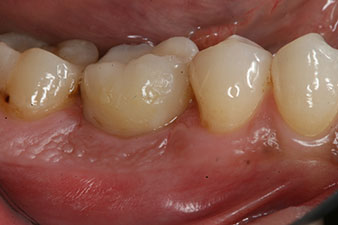

corona de composite

Figura 9: La corona de composite definitiva se adhirió en el laboratorio a un pilar híbrido PEEK, por lo que pudo atornillarse de inmediato.

radiografía de control

Figura 10: La radiografía de control muestra que se había producido una correcta osteointegración y que la corona se había atornillado sin dejar hendiduras.